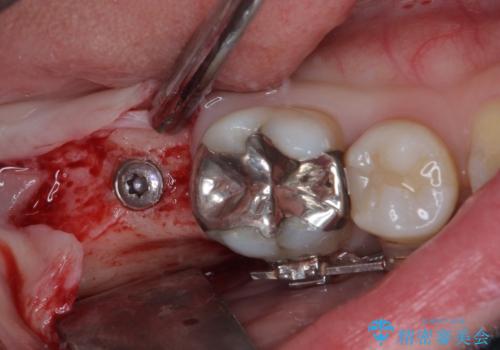

- 口元の突出感と奥歯の欠損を気にして来院された患者様です。

口元の突出感改善には、上下左右の第一小臼歯4本を抜歯し、奥歯の欠損部には矯正治療の途中でインプランを埋入していくこととしました。

矯正治療の後半にインプラント埋入を行うことで、トータルの治療期間を短縮することができました。